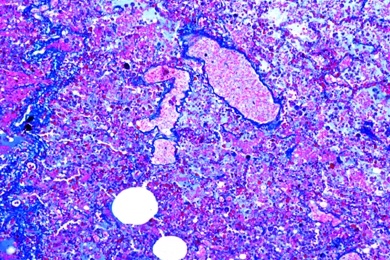

Pathologische Histologie des Menschen, Grundserie Teil II, 40 Präparate

4201e Lebermetastasen eines Melanosarkoms des Mastdarms 4202e Maligner Tumor der Gallenblase,